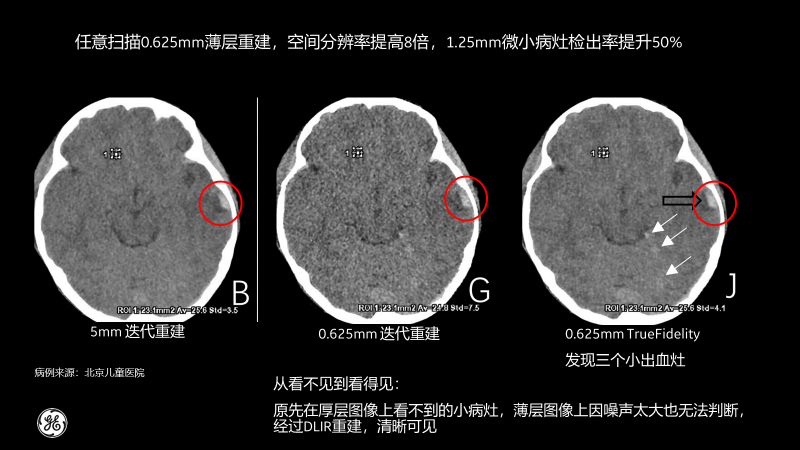

相比傳統(tǒng)CT圖像對(duì)腹部檢查一般都選擇5mm厚層重建,TrueFidelity可對(duì)任意體型任意部位的檢查進(jìn)行0.625mm的薄層圖像重建,真實(shí)還原圖像的解剖細(xì)節(jié)和紋理,提高微小病灶的發(fā)現(xiàn)幾率,有助于早診早治,極大提高醫(yī)生的診斷信心。

北京兒童醫(yī)院的測(cè)試病例也顯示,經(jīng)過(guò)TrueFidelity,任意掃描0.625mm薄層重建,空間分辨率能提高8倍,1.25mm微小病灶檢出率提升50%,最終額外發(fā)現(xiàn)了3個(gè)之前看不到的微小病灶。